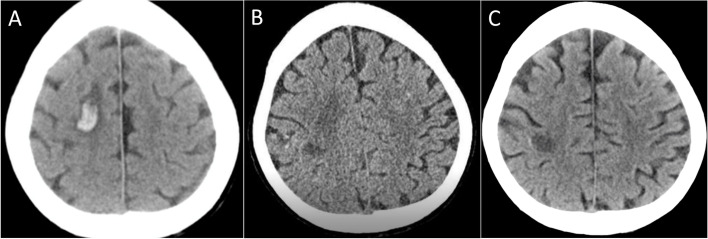

Fig. 2.

Changes in brain computed tomography (CT) findings. A On admission showing hemorrhagic cerebral infarction. B Before operation showing the regression of cerebral hemorrhage. C Before discharge showing no recurrence of cerebral hemorrhage

She was diagnosed with infective endocarditis complicated with systemic multiple abscesses due to CA-MRSA and C. albicans. However, because of brain hemorrhage and low platelet count, primary surgical treatment was considered intolerable. Therefore, medical antibacterial treatment with fluconazole (FLCZ), meropenem (MEPM), and vancomycin (VCM) was introduced, and heart failure treatment with mechanical circulatory support and renal replacement therapy was continued (Fig. 3). A steroid therapy was also introduced for the destructive thyroiditis. Hemodynamics were stabilized, and ECMO and IABP were weaned off on day 5 of admission. Renal function also normalized, and the renal replacement therapy could also be discontinued. The platelet counts gradually increased and reached 10.0 × 104/µL, and surgical treatments were conducted on day 26 of admission after regression of cerebral hemorrhage was confirmed by brain CT scan (Fig. 2B).

After the operation, the blood culture became negative for the first time during the course and kept being negative except for one occasion when it grew C. albicans 2 weeks after the operation (Fig. 3). The postoperative antibacterial treatment consisted of 4 agents with FLCZ, MEPM, micafungin, and VCM, and it was decreased to 2 agents (FLCZ and VCM) 2 weeks after the operation. Despite the negative blood culture, the white blood cell counts remained high, and C-reactive protein remained positive in the blood test (Fig. 3), and contrast-enhanced CT scan revealed recurrence of multiple skeletal muscle abscess. Therefore, the abscess drainage was performed by orthopedics team again 3 weeks after the operation (Fig. 4F). The inflammatory signs in the blood test subsided thereafter, and repeated CT scan revealed no recurrence of the abscess. Postoperative transthoracic echocardiography showed a normal left ventricular contractility with left ventricular ejection fraction of 63%, no vegetation, no paravalvular leakage of the mitral valve, and mild tricuspid regurgitation. Finally, the antibiotics were changed to oral trimethoprim-sulfamethoxazole combination, and the patient was discharged to a rehabilitation facility on 114 days. Brain CT scan before discharge revealed no recurrence of cerebral hemorrhage (Fig. 2C). Genomic analysis of MRSA isolated from blood revealed Staphylococcal Cassette Chromosome mec (SCCmec) IVc containing the mecA gene responsible for methicillin resistance and also the virulence gene encoding PVL.